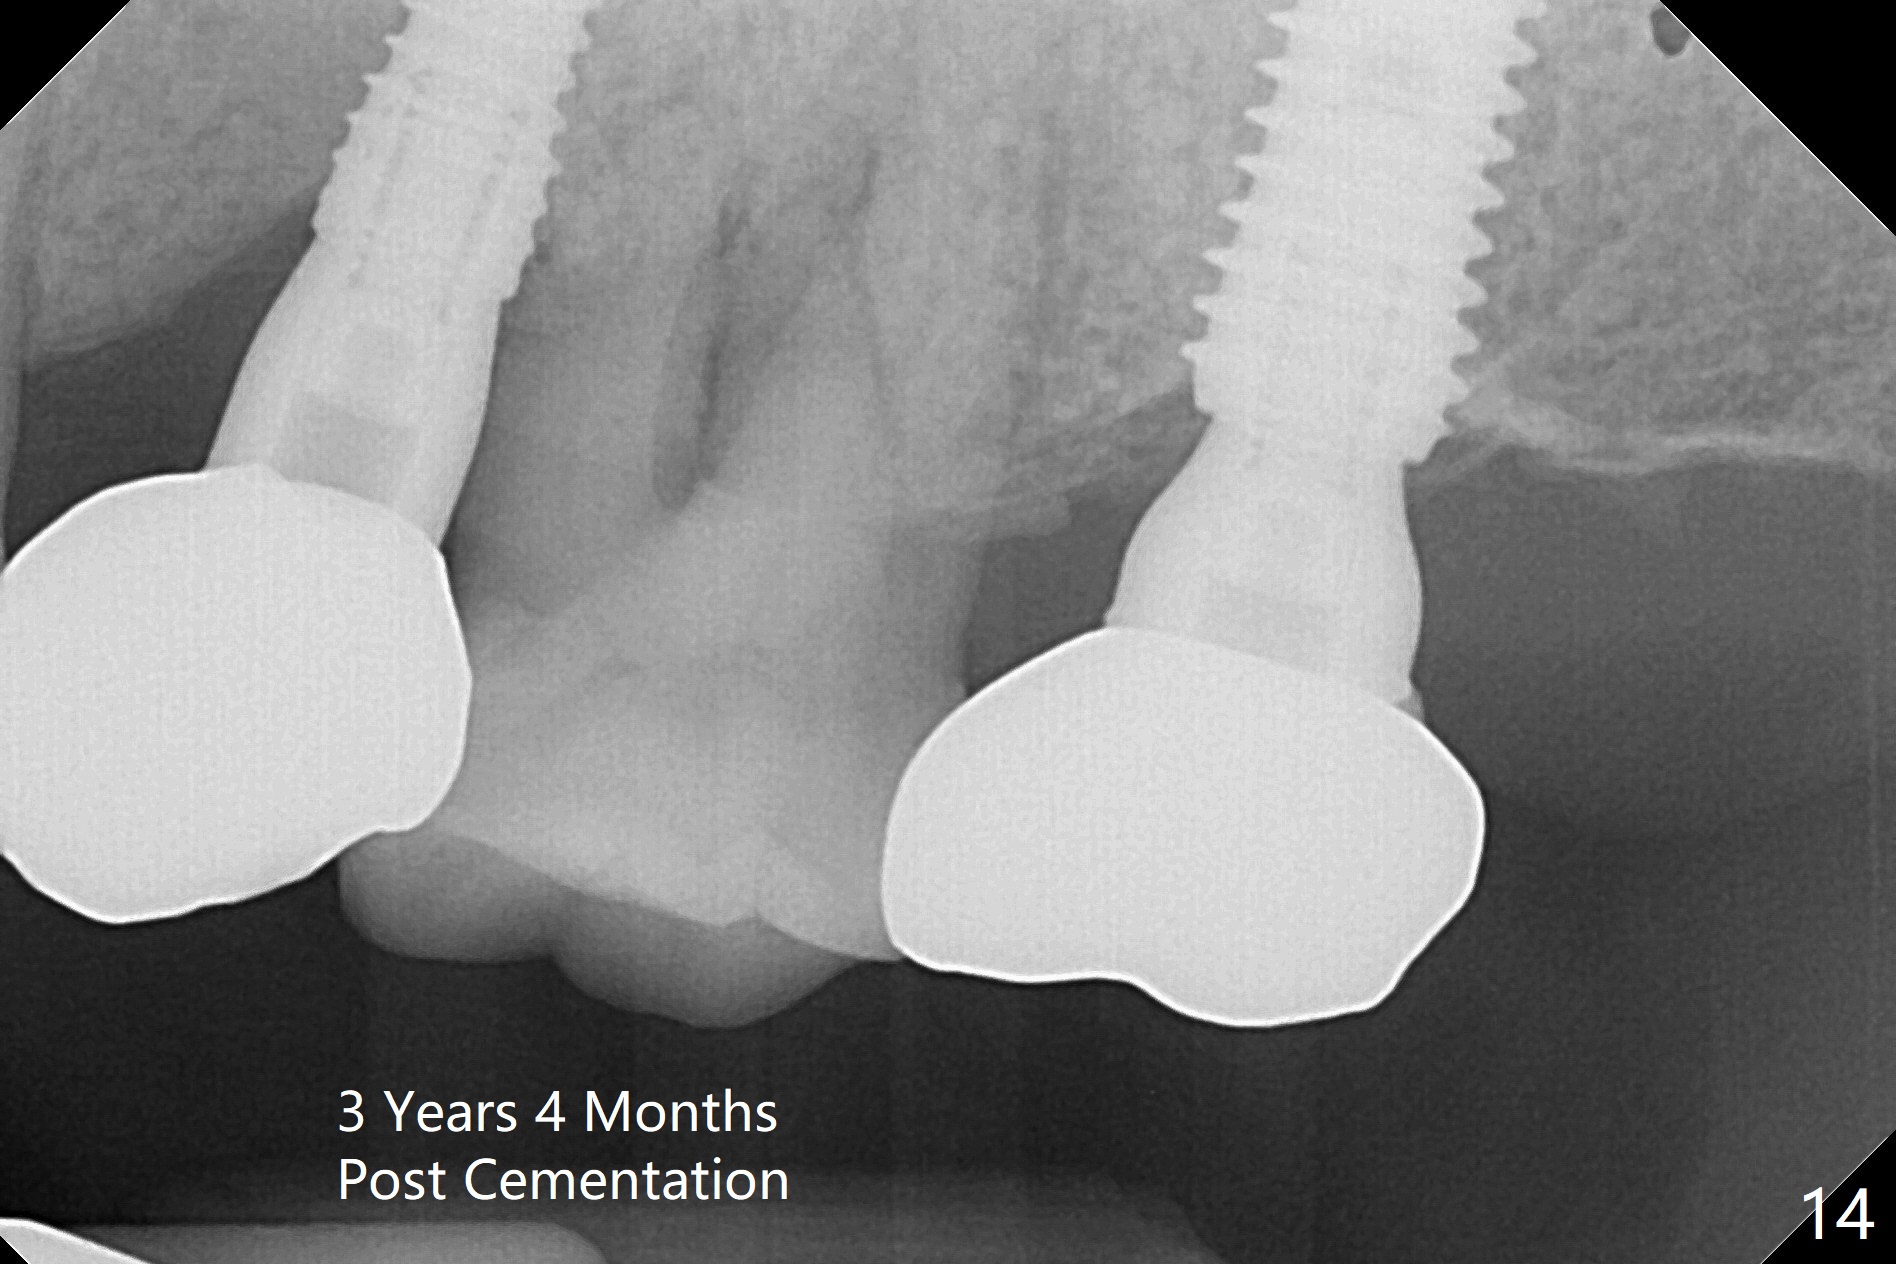

Initial osteotomy depth is 18 mm (Fig.1 green line) with 9 mm in the native bone (red line). The bone density feels to be low. There is at least 2 more mm bone apically (pink line). The depth is increased by 2 mm so that when a 3.8x15 mm implant is placed, there is 10-11 mm implant/bone contact (Fig.2 red line). There is large bony defect (Fig.3 *), which is bone grafted (Fig.4 *). Finally a longer abutment is placed (4.5x5.5(5) in Fig.4 vs. 4.5x4(5) in Fig.2,3). The 5 mm cuff does not look too long buccally (Fig.5) or palatally (Fig.6). To prevent postop buccal gingival overgrowth (2), the buccal margin of an immediate provisional is subgingival (Fig.7-9 *). Bone density between #13 and 14 appears to increase 3 months postop (Fig.10). The implant seems to be equi-crestal (Fig.11 ^). There seems to be more bone growth (i.e., decreasing gap) 6 months postop (Fig.12). Impression is taken. A crown is delivered nearly 7 months postop (08/07/2017). While there is minimal bone loss at #13 and 15 three years and 4 months post cementation, the tooth #14 and 18 are mobile (Fig.13,14).